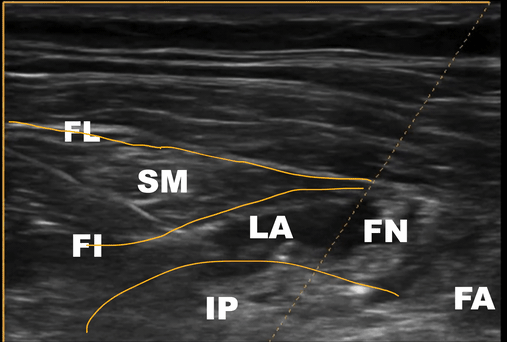

Clip 2 - Sono-Anatomy of the Performed Block with Annotations

FL- Fascia Lata, FI- Fascia Iliaca, LA- Local Anaesthetic, SM- Sartorius Muscle, IP- Iliopsoas Muscle, FN- Femoral Nerve, FA- Femoral Artery

A - Fascia Lata B - Sartorius Muscle C - Fascia Iliaca D - Hydro-dissection/Local Anaesthetic E- Femoral Nerve F- Iliopsoas muscle G- Femoral Artery